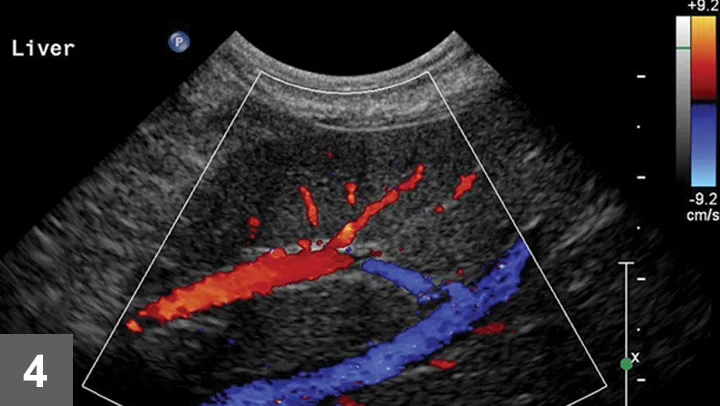

Once the image area is optimized, turn on color flow Doppler to ensure there are no major vessels in the area of interest (Figure 4). The hepatic and portal veins—but not the distribution of the hepatic artery—can be visualized on a standard gray-scale 2-dimensional ultrasound image. Angle to the right and left to ensure that there are no major vessels within the target area. Turn off imaging compounding to ensure accurate needle-tract and needle-tip placement at depth in the liver.

Color Doppler of a potential biopsy area in the liver. On account of the presence of large portal veins (colored in red—flow toward the transducer) and hepatic veins (colored in blue—flow away from the transducer), this area was not chosen for biopsy.

Optimize the image before the procedure to know exactly where the least amount of vasculature is, relative to the parenchyma, to be obtained. This includes using the highest frequency transducer, ensuring the biopsy area is within several inches of the surface, reviewing the biopsy plan on screen with the image frozen for depth of distal or deep-needle placement, and using color flow Doppler or power Doppler to check that no large vessels are in the sample area.

Biopsy needle tract within the patient after firing and just before removing the biopsy device (B). Post-biopsy hemorrhage often collects between hepatic lobes as seen in this image (white arrow heads) (C). The echogenic fluid represents acute hemorrhage. Color flow Doppler post-biopsy ensures there is no persistent hemorrhage in the peritoneal space (D). Power Doppler imaging is the most sensitive form of Doppler to detect the presence or absence of blood flow.